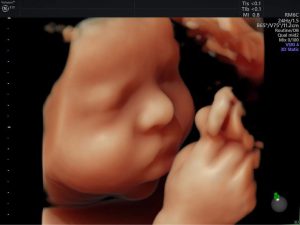

Siêu âm 4D giúp mẹ được nhìn thấy sự phát triển thai nhi và biết ...